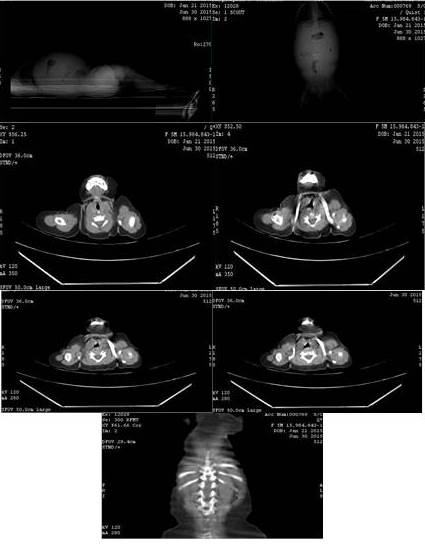

Se trata de lactante menor femenino de 5 meses de edad natural y procedente del Estado Apure, con inicio de enfermedad actual en junio de 2015 cuando comienza a presentar distensión, dolor abdominal difuso y evacuaciones líquidas, por lo cual es llevada a centro de salud de su localidad, donde descartan patología infecciosa; sin embargo, por persistir aumento del perímetro abdominal y palpar una masa sólida en hipogastrio y fosa iliaca izquierda se realiza ecosonograma abdominal y tomografía axial computarizada (TAC) de abdomen con doble contraste que reporta ascitis severa y lesión ocupante de espacio (LOE) abdominal izquierdo; por lo que se plantea diagnóstico tumor de ovario izquierdo (Figura 1, 2).